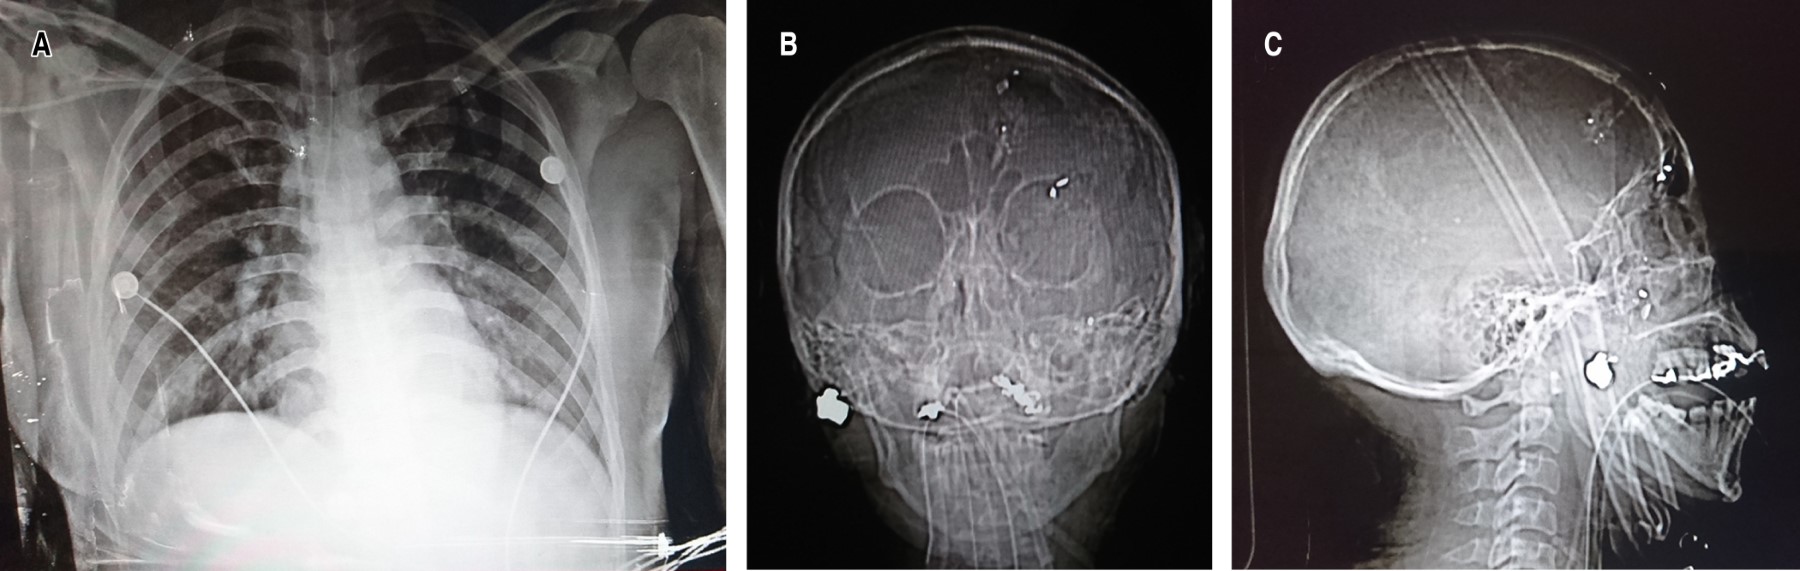

La radiografía de tórax no muestra alteraciones, en las radiografías de cráneo se evidencia proyectil de arma de fuego (PAF) a nivel de pómulo izquierdo en la radiografía anteroposterior y lateral de cráneo (Figura 1).

Se realiza estudio tomográfico de cráneo en el que se muestra proyectil en la región maxilar derecha, con esquirla en parénquima frontal izquierdo, por lo que se realiza esquirlectomía con craniectomía por el Servicio de Neurocirugía.